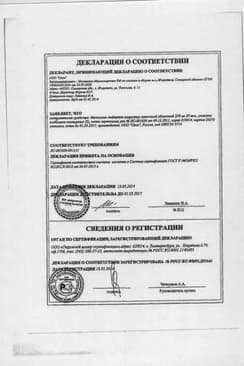

Сертификаты